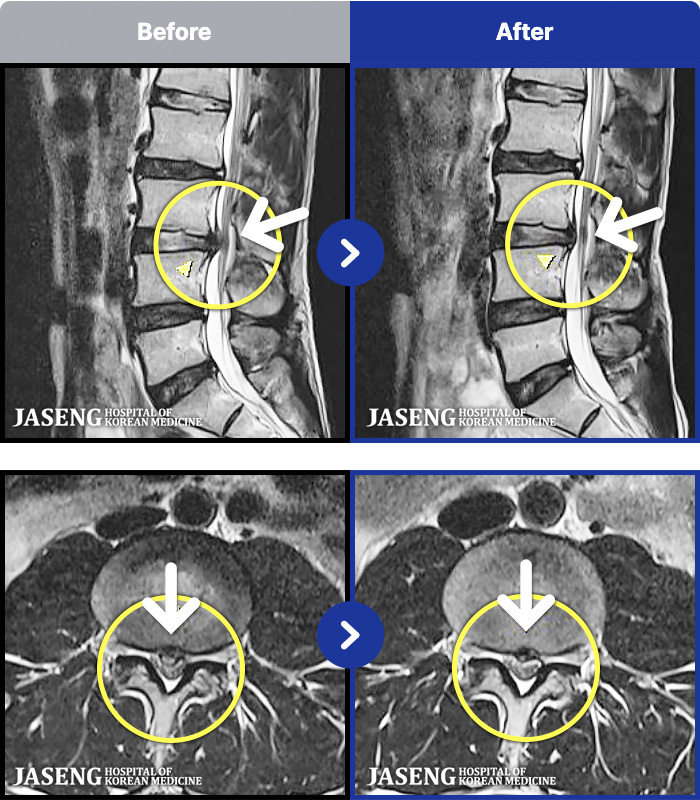

ȯںп Ǹ ǿ ԿǾ, ο ġ ۿ Ƿ ġḦ Ͻñ ٶϴ.